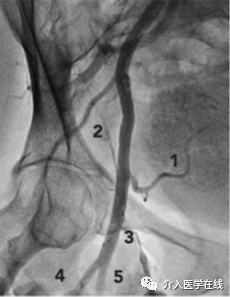

1. 定位动脉搏动最大点。将止血钳头端放置在股骨头中部的预期穿刺部位(如图 2所示),大部分非肥胖患者的 CFA 分叉通常位于此处。使用透视非常重要,因为它可确保穿刺部位位于腹股沟韧带下方至少 1 cm 处。如果穿刺位置过高,腹膜后出血的风险将急剧增加。

图2